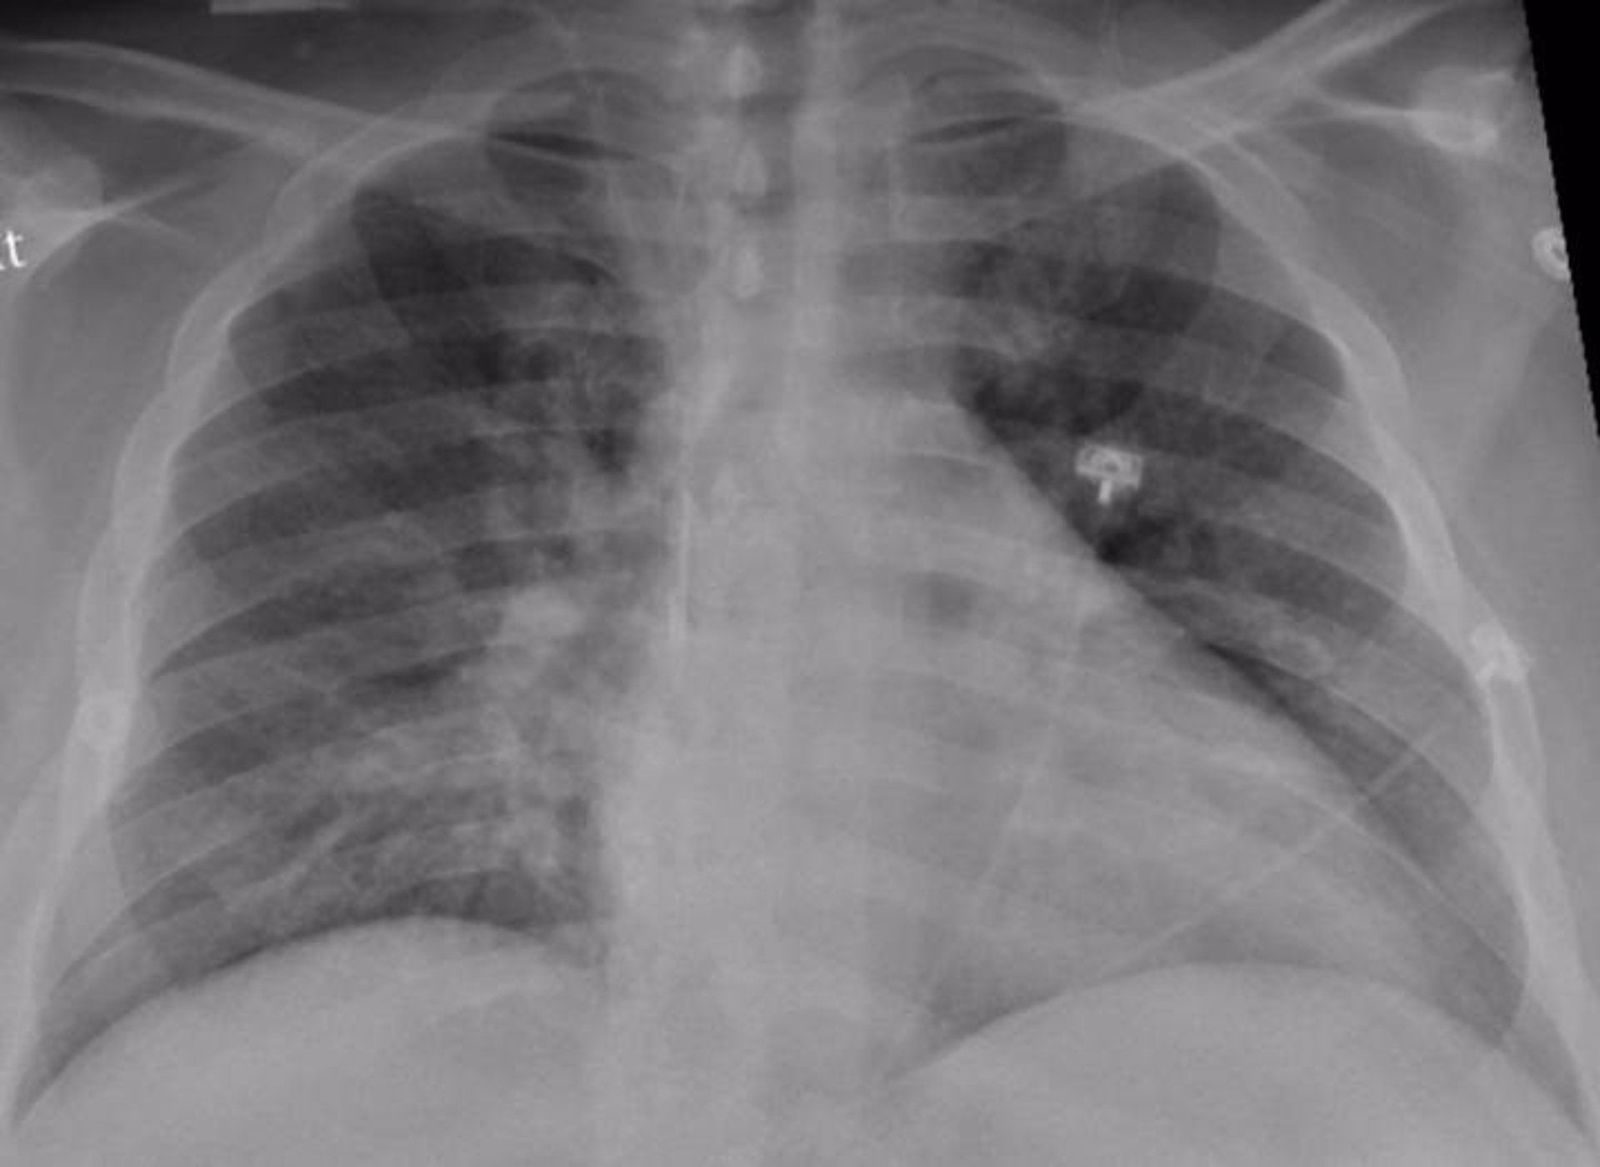

Imagen del tórax de un paciente positivo en COVID-19 con neumonía.